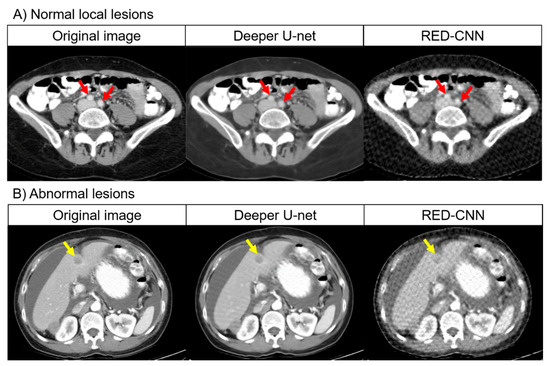

The results of the visual evaluation are shown in Figure 4 and Figure 5 and Table 5 and Table 6. For all items of the visual evaluation, deeper U-net scored better than that of RED-CNN for both readers as shown in Table 7.

Figure 4.

Visual evaluation of entire CT image quality by the two readers using different deep learning algorithms.

Figure 5.

Visual evaluation of normal local lesions and abnormal lesions by the two readers using different deep learning algorithms.